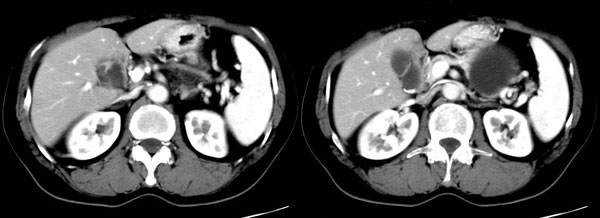

ct平扫加增强扫描:胆囊折叠,壁厚,其内见结石。胰腺体尾部见一5.8x7.5cm囊性肿物,ct值12hu,壁薄,增强扫描未明显强化,胰头不大,强化均匀。

参照ct片,经皮穿刺,抽出透明液体60ml,随后置入引流管引流,囊液细胞学检查阴性,胰酶检查阴性。采用无水乙醇灌注治疗。4天后囊腔闭锁,无液体渗出,予以拔管。

置管后造影,显示囊腔直径约5cm,囊壁光整,正位、双斜位造影均未见造影剂外溢,与胰腺无交通